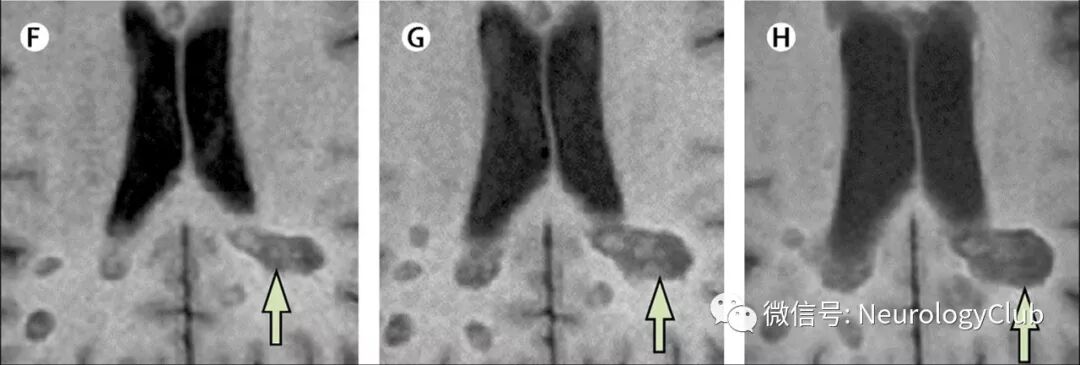

MS病灶通常分布在两个半球,早期多为轻度不对称性。病灶可见于中枢神经系统任何部位,相对于其他引发白质病变的疾病而言,MS常累及特定的白质区域,如脑室周围、皮质下白质、胼胝体、幕下(尤其是脑桥和小脑)和脊髓(尤其是颈段)。MS典型病灶(绿旗征)与非典型病灶(红旗征)见表2,相关影像学描述见图1-5。

图2:MS患者皮质/近皮质典型和非典型病灶以及不应该计数在内的病灶;左上:绿旗征:提示MS的近皮质(A)和皮质(B)病变;右上:(C)白质病灶未接触皮质或位于皮质内(皮质下);底部:红旗征:(D)皮质下和深部白质多发病灶,提示小血管病;(E)进行性多灶性白质脑病累及不同脑叶灰质和白质,边界模糊不清;(F)扩大的血管周围间隙,为点状或条纹状边界清晰的脑脊液样信号;(G) T2WI低密度提示微出血导致的含铁血黄素沉积;(H)中枢神经系统血管炎可见T1WI多发软脑膜和皮质高信号伴梯度回波序列低信号;JC/CL=近皮质/皮质

图3:MS患者幕下典型和非典型病灶;左:绿旗征:(A)幕下病灶;右:红旗征:(B)见于小血管病的对称性脑桥中央病灶;(C)NMOSD导水管周围病灶;(D)NMOSD极后区病灶;(E)MOG抗体相关疾病中脑-间脑病灶;(F)神经白塞病邻近四脑室底的大的卵圆形病灶